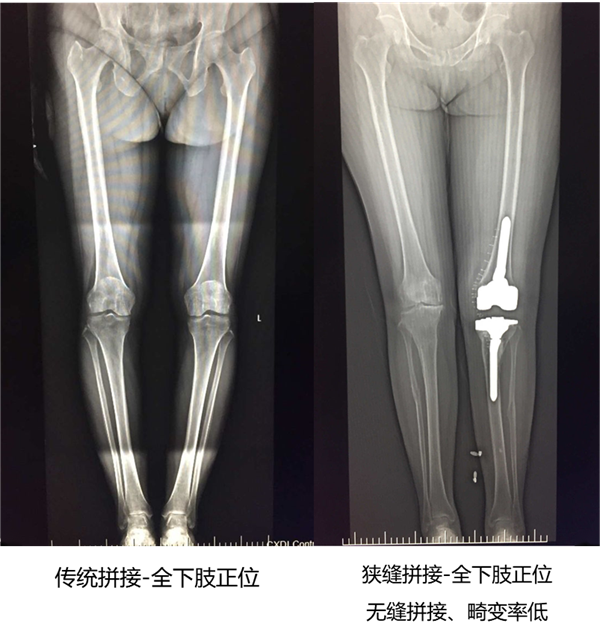

1. SLOT狭缝拼接检查时,X线以近乎垂直的角度投射到被检部位,相比平行拼接检查投影无畸变,能准确反映骨骼的真实结构,因而影像能完成更精确的测量,且密度均匀,能够为术前规划和术后评估提供更好的影像信息。